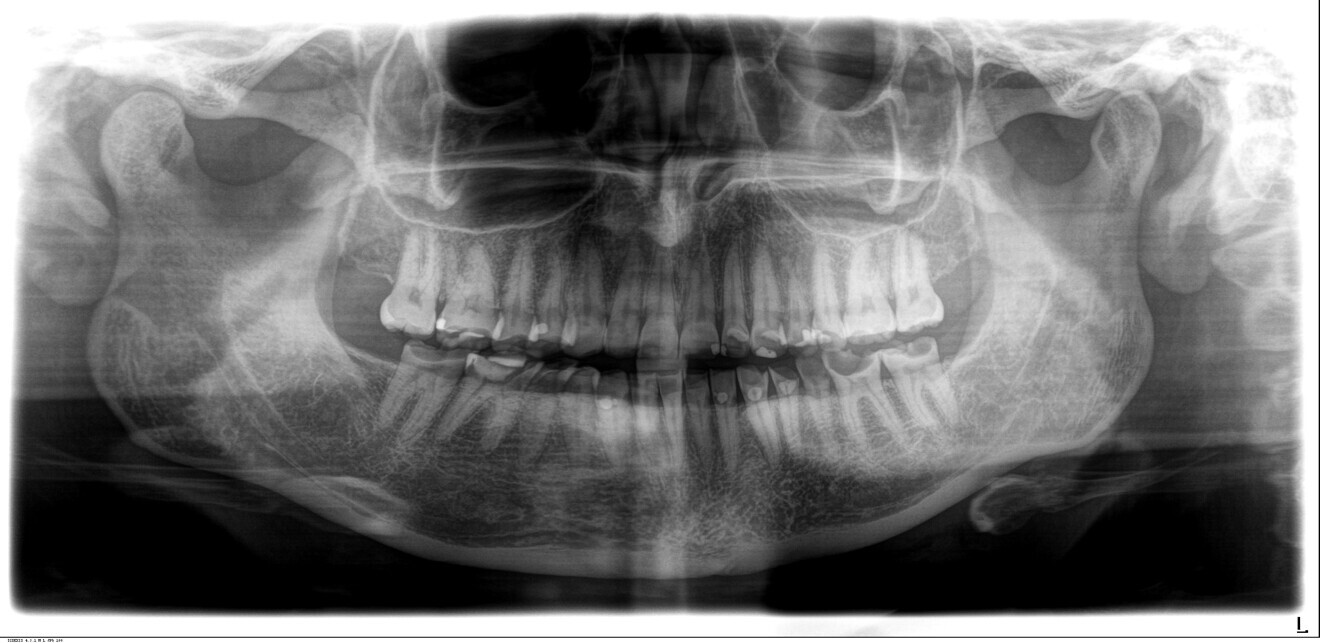

Fig. 1f: Dental panoramic tomogram.

The clinical and radiographic examination revealed pronounced erosive defects on all teeth (Figs. 1a-f). To prevent nocturnal wear of the remaining tooth structure, an occlusal splint had been prepared by the patient’s general dentist in the past. Quick screening for temporomandibular disorder using the tool developed by the German Society of Craniomandibular Function and Disorders was carried out and revealed no functional abnormalities. The diagnosis was generalised, highly pronounced erosion due to exogenous acid (cola), abrasion and attrition with decreased OVD, multiple carious lesions, dentine hypersensitivity, gingivitis and compromised aesthetics.